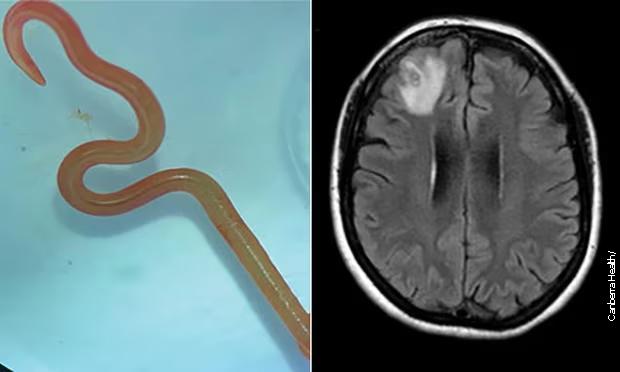

Nakon još jednog snimanja magnetnom rezonancom, lekari su odlučili da izvrše kraniotomiju i uklone ono što su identifikovali kao živog crva unutar pacijentovog mozga.

Tokom postupka, jedan od hirurga je uspio pažljivo da ukloni dugog, bijelog parazita netaknutog, dok se migoljio.